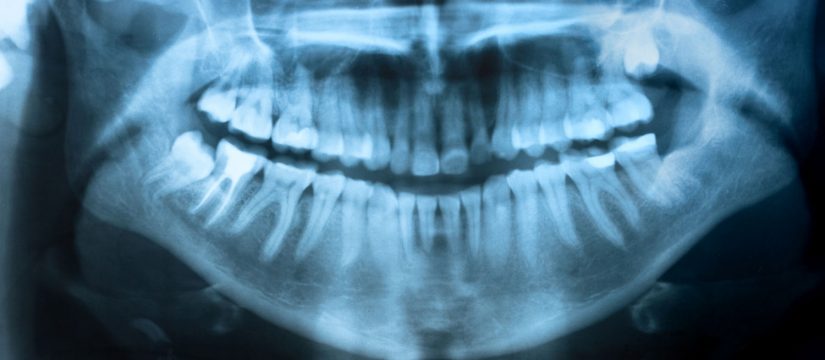

X-Rays

Either directly or indirectly, we are all exposed to natural radiation in our environment. Our digital x-rays produce a significant lower level of radiation compared to the dental x-rays of the past. Not only are digital x-rays better for your health, they’re faster and more comfortable and reliable. We usually recommend a full mouth series…